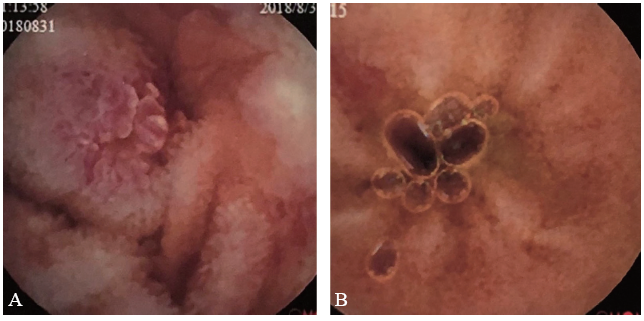

图3 一例EG患者治疗前后结肠镜对比图

A、B:结肠镜显示回盲部、回肠末端治疗前散在糜烂及溃疡;C、D:治疗后结肠镜显示回盲部溃疡愈合、回肠末端黏膜光滑

X线胸片提示双肺未见异常。胃镜检查显示胃底、胃体、胃窦及十二指肠仍有多发散在溃疡,直径约0.5 ~ 0.8 cm(图1A、B),病理活组织检查(活检)提示胃黏膜呈慢性活动性炎症,固有层较多嗜酸性粒细胞浸润,约60个/高倍镜视野(图2A)。结肠镜显示回肠末段、升结肠、横结肠、乙状结肠及直肠局部黏膜充血、水肿,多发散在点、片状糜烂及溃疡,直径约0.1 ~ 1.0 cm,病变间隔有正常黏膜(图3A、B)。病理活检提示肠黏膜呈慢性活动性炎症,固有层较多嗜酸性粒细胞浸润,其中回盲部约100个/高倍镜视野,结肠约60个/高倍镜视野(图2B、C)。胶囊内镜显示小肠黏膜多发散在糜烂、溃疡灶,溃疡形状不规则,直径约0.3 ~ 0.8 cm,病变呈跳跃性,病变之间有正常黏膜(图4A)。

全腹部增强CT提示肠系膜周围见多发肿大淋巴结,未见“靶征”“木梳征”等征象。综合病史、临床表现及上述检查结果,拟诊为EG,给予口服泼尼松15 mg,每日2次。1周后患者腹痛症状显著改善,复查嗜酸性粒细胞绝对值0.01×109/L,嗜酸性粒细胞百分比1.1%。患者出院后继续口服糖皮质激素维持治疗。4个月后患者复诊时腹痛症状基本缓解,复查胃镜(图1C、D)、结肠镜(图3C、D)及胶囊内镜(图4B)均显示消化道溃疡大部分愈合,溃疡数量较前明显减少,病变范围较前明显缩小。半年后随访患者已停用糖皮质激素,腹痛等症状未复发,食欲及大便情况也较前明显改善。最后诊断:EG。